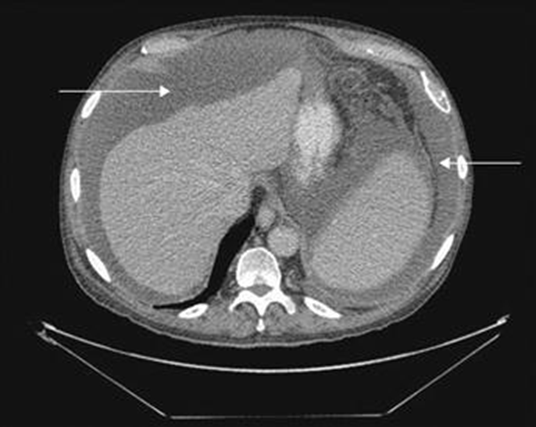

This range of Houndsfield units may suggest simple ascites without complications (will accept any number in the range as well). Depicted below.

-10 to 10 HU

Can be found on CT at only 50-75mL of fluid present in the peritoneal space, but at this levels may be “free fluid” or physiological. May represent any cause of exudative fluid but is typically seen surrounding the anterior lobe of the liver as well at more advanced stages. This would NOT include fluid that is loculated or exudative fluid.